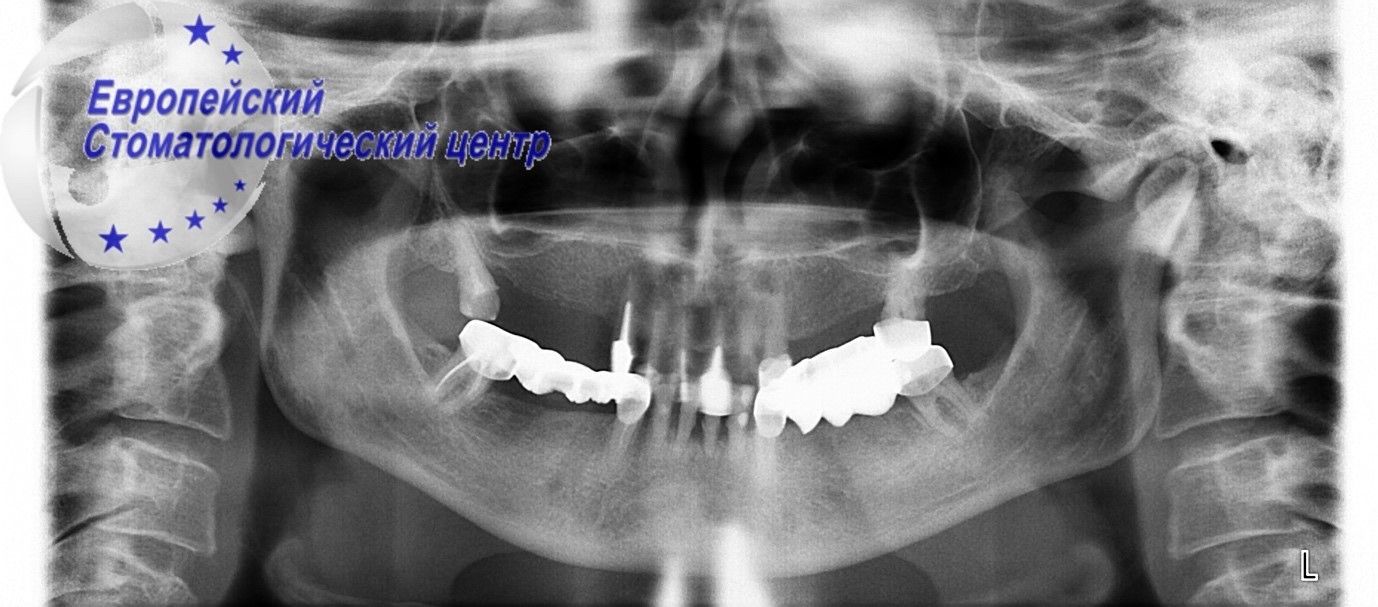

Встановлено діагноз, прогресуючий генералізований пародонтит. Було прийнято рішення про видалення всіх наявних зубних елементів з подальшою експрес імплантацією зубів. Операцію по встановленню імплантів ускладнювало ще й наявність інфікованих тканин у ротовій порожнині. Після видалення зубів була проведена дезінфекція лазером і кюретаж лунок видалених зубів. Лікарям Європейського стоматологічного центру вдалося за одне хірургічне втручання видалити пошкоджені одиниці на верхній і нижній щелепах, малоінвазивно, без додаткових розрізів і ускладнень встановити 17 імплантів, і через день — тимчасові незнімні ортопедичні конструкції (див. малюнки 3-4).

Малюнок 3

Малюнок 4

На даний момент пацієнт очікує повної інтеграції імплантів і встановлення постійних незнімних конструкцій. Швидка (за 3 дні) реабілітація пацієнта досягнута завдяки багаторічному досвіду, постійному вдосконаленню та наявності сучасного стоматологічного обладнання в Європейському стоматологічному центрі.